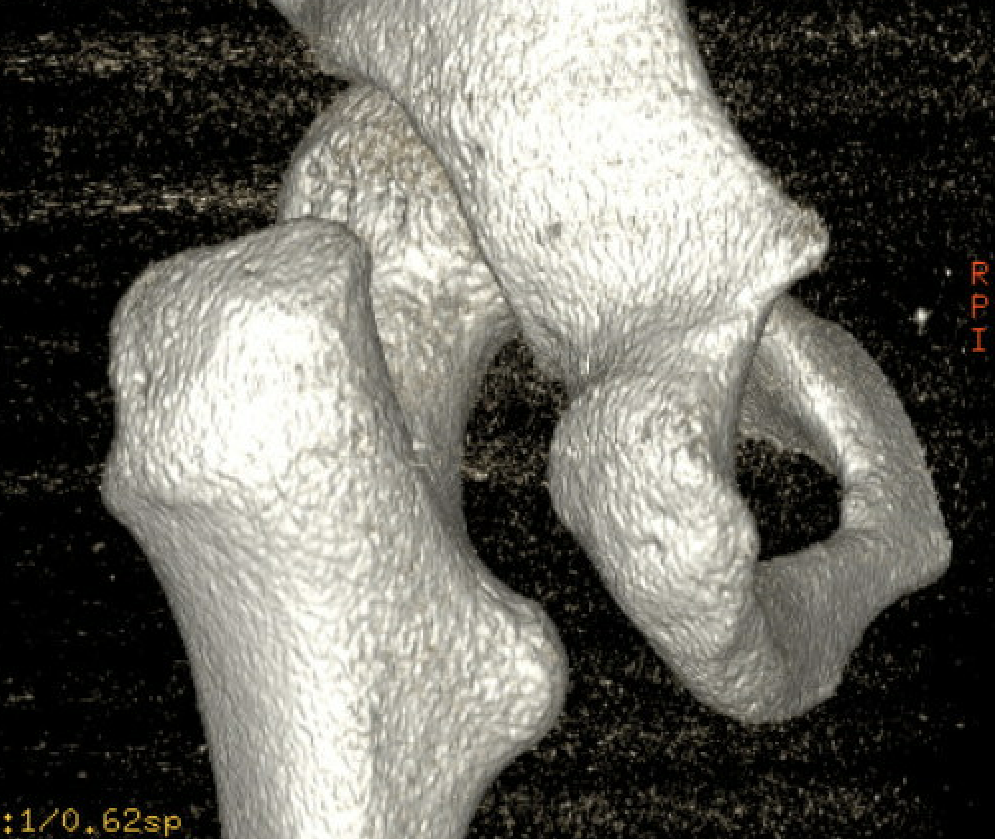

Narrowing of the ischiofemoral space between lateral ischium and lesser trochanter

Primary

- enlarged lesser trochanters

- increased proximal femoral anteversion

- coxa valga

- proximal femoral fractures

- osteochondromas

- THA